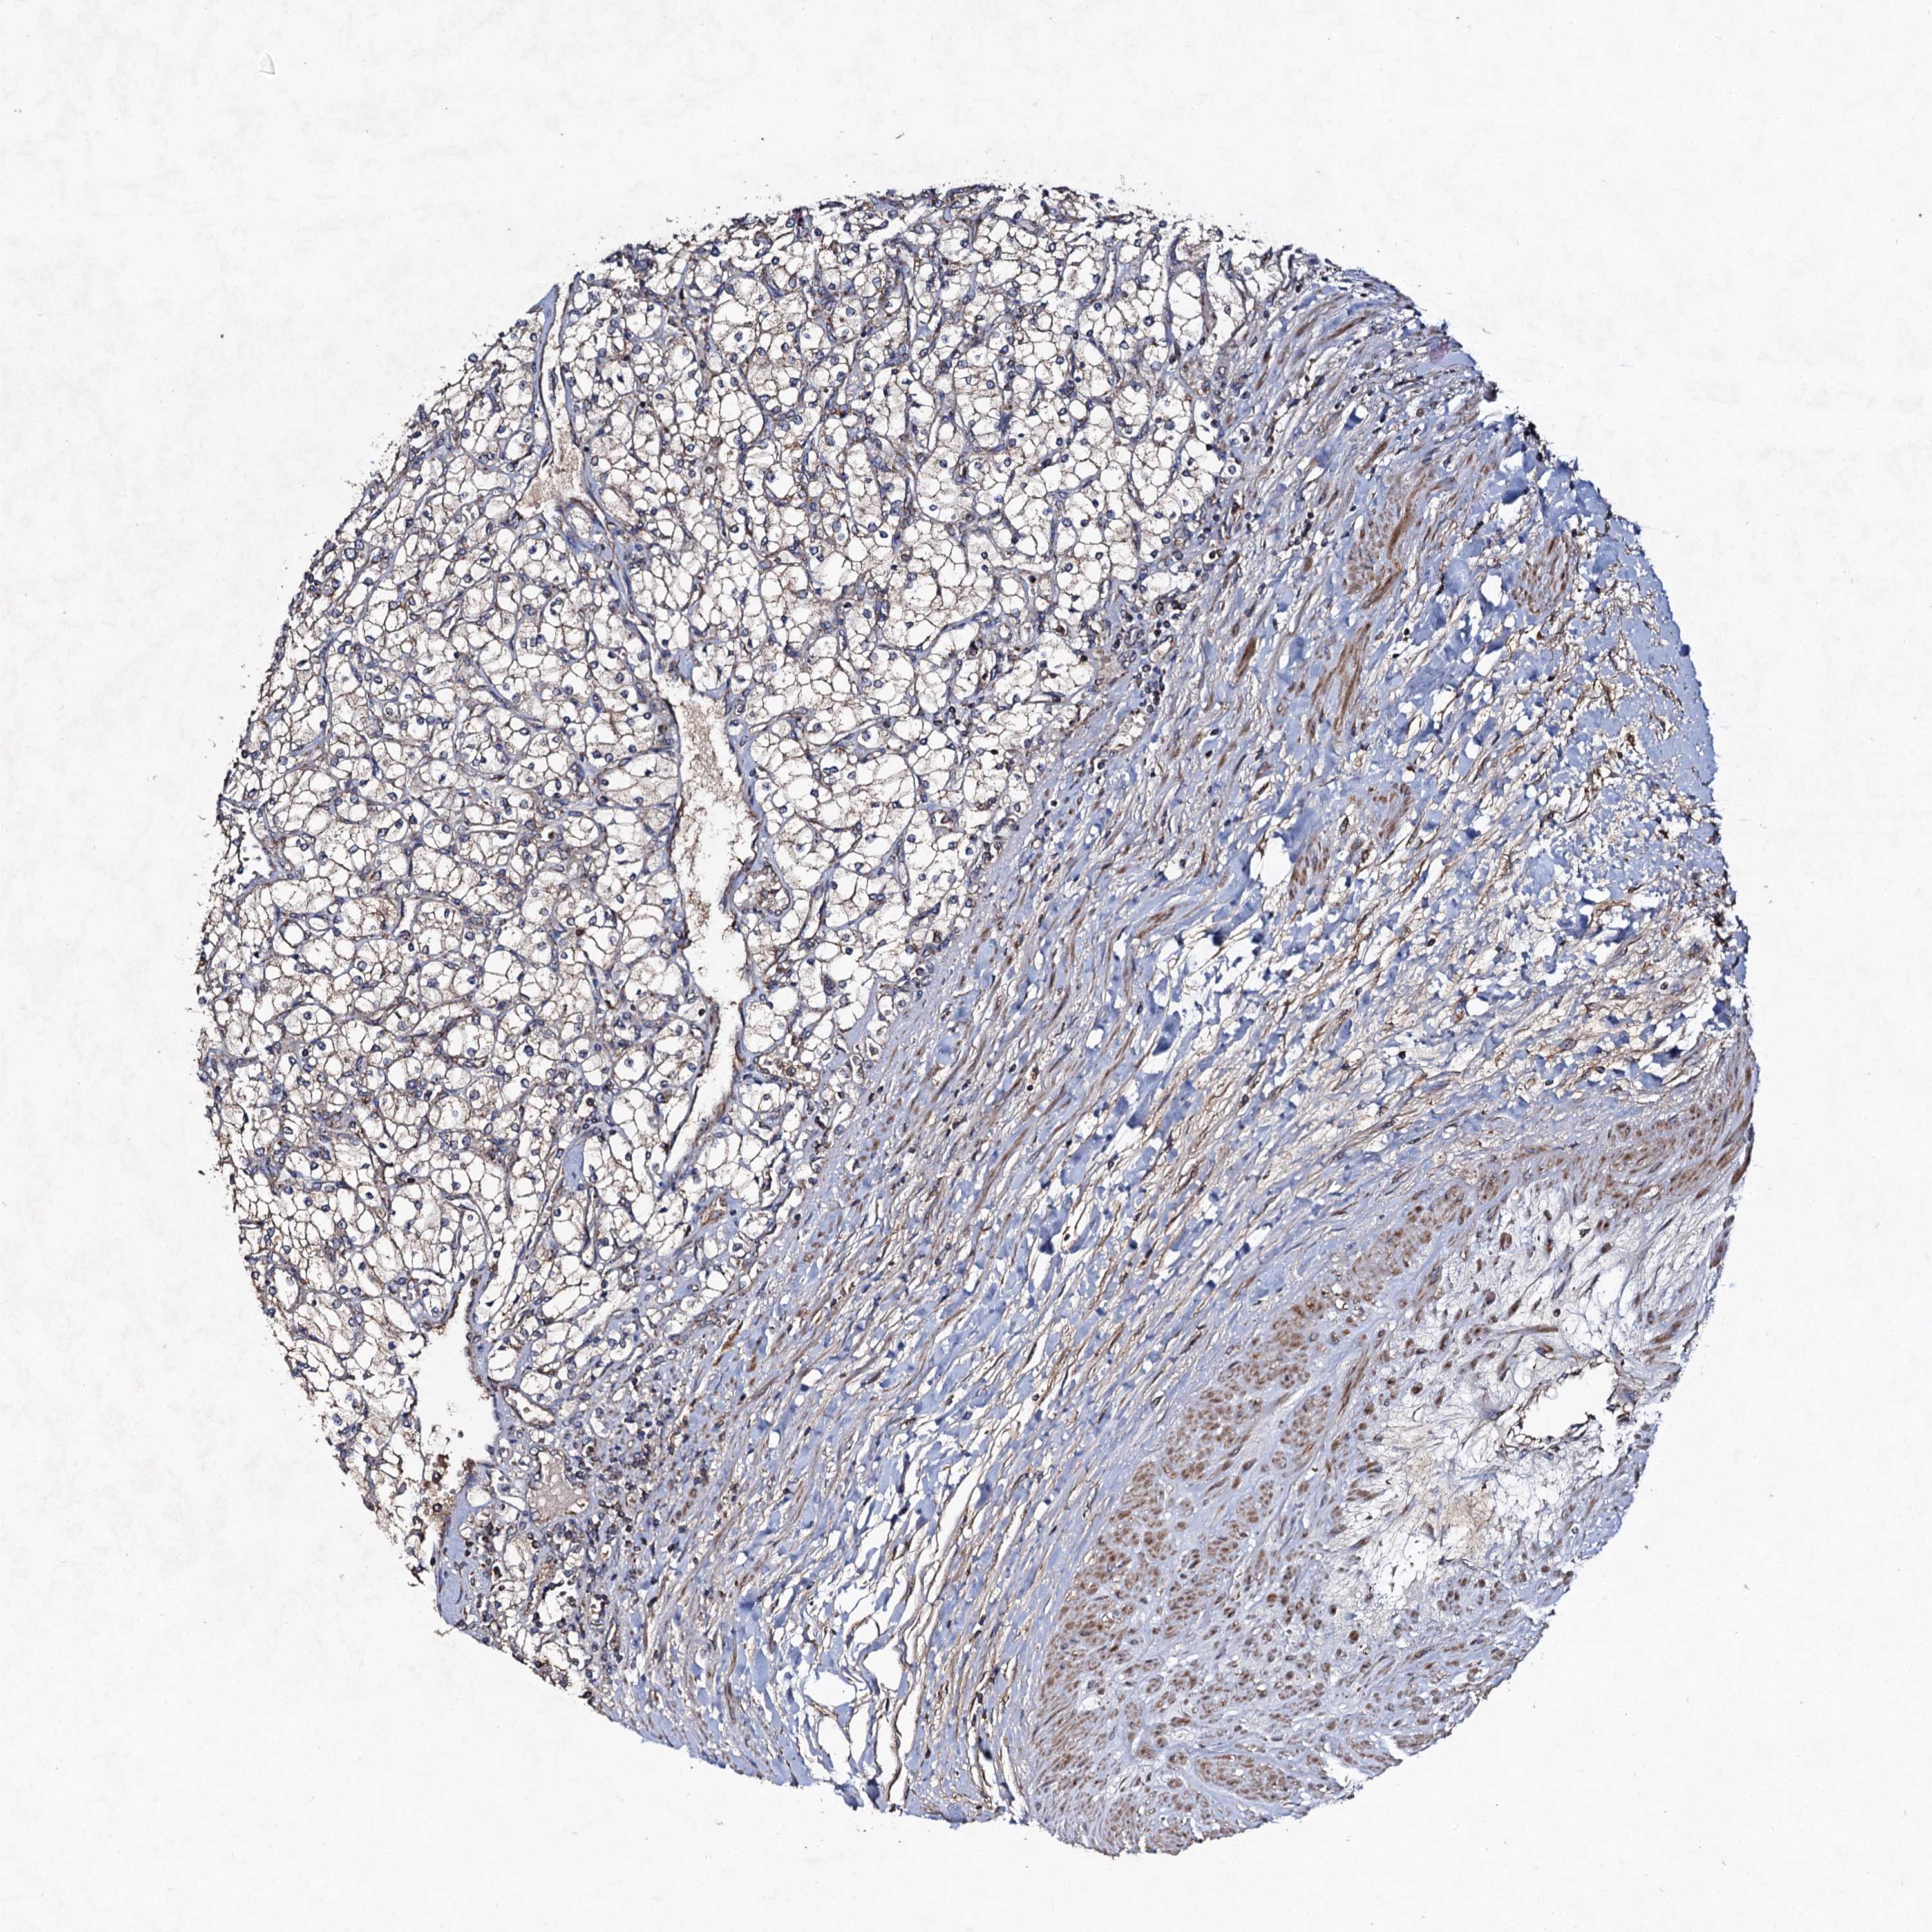

CANCER RENAL CANCER Show tissue menu

KICH TCGA KIRC TCGA KIRC VALIDATION KIRP TCGA PROTEIN RCC CPTAC PROTEIN EXPRESSION